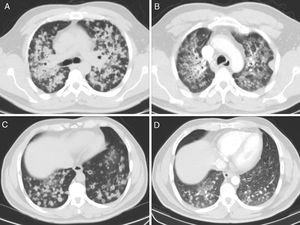

A continuación se presenta el caso de un paciente natural de Ecuador, de 49 años de edad, sin antecedentes personales de interés, no fumador y sin contactos conocidos con pacientes afectos de tuberculosis. Consultó por un cuadro de tos crónica productiva de 10 meses de evolución, con esputos mucopurulentos y ocasionalmente hemoptoicos, además de intensa hiporexia y pérdida de 3kg de peso. En la radiografía de tórax se apreciaban infiltrados pulmonares bilaterales con algunas imágenes pseudonodulares mal definidas, de predominio en los lóbulos superiores. Ingresó en régimen de aislamiento respiratorio con sospecha inicial de tuberculosis, siendo las baciloscopias de esputo negativas. Tras comprobar en la TAC de tórax la existencia de múltiples opacidades nodulares pulmonares bilaterales (fig. 1A y C), la mayoría de ellas cavitadas, se realizó broncoscopia que no mostró hallazgos patológicos en la revisión bilateral exhaustiva. Se llevó a cabo un estudio citológico de las muestras de lavado broncoalveolar, diagnosticándose de adenocarcinoma de pulmón con patrón micropapilar. La deleción del exón 19 fue positiva, mientras que el resto de las mutaciones estudiadas fueron negativas (L858R, T790M, G719A/C/S, exón 20, S768I y L861Q, ALK y ROS1). El paciente comenzó tratamiento con gefitinib, con buena respuesta clinicorradiológica a los 4 meses (fig. 1 B y D).

Nuestro caso ofrece peculiaridades al tratarse de una presentación radiológica infrecuente. Por ello, consideramos que el adenocarcinoma de pulmón ha de incluirse en el diagnóstico diferencial de este patrón radiológico.